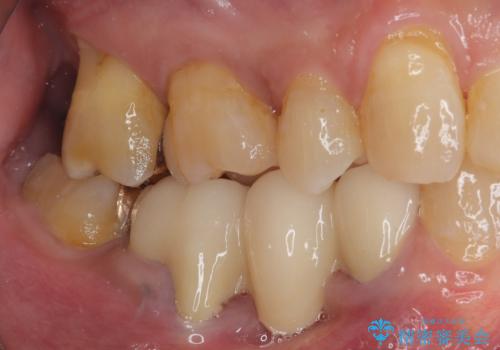

奥歯の欠損と前歯のデコボコを治したい インプラントと矯正治療の総合歯科治療

- 下顎両側の欠損と上顎前歯のデコボコを気にして来院された患者様です。

デコボコは今まで気にせずにいたそうですが、奥歯の欠損改善を機に、矯正治療に興味があるので、相談したいとのことでした。

銀歯やむし歯治療されている歯を抜歯する治療計画としたため、やや時間はかかりましたが、治療後の仕上がりには大変満足していただけました。